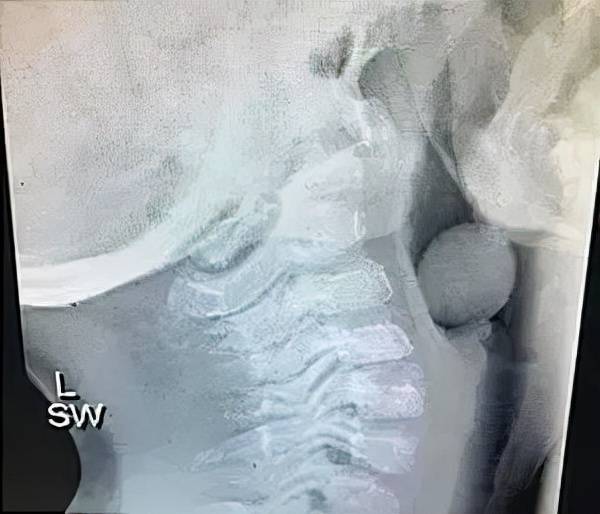

它们的特点就是表面光滑 , 且可以挤压 。 一旦堵住气管 , 医生很难让它上下移动 , 大大增加取出难度 。

(被葡萄卡住的X光图)

吃的时候 , 要切成不超过1cm的长度 , 大约就是把一个葡萄四等分 , 这样的大小孩子吃起来更安全 , 也完美避开了表面光滑的问题 。